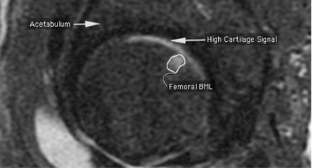

The objective of this study was to describe the cross-sectional and longitudinal relationship between hip bone marrow lesions (BMLs), high cartilage signal, and hip and knee pain. One hundred ninety-eight participants in the Tasmanian Older Adult Cohort Study with right hip MRI conducted at two time points, approx. 2.3 years apart, were included. Short T1 Inversion Recovery MR images were used to quantitatively measure hip BML size and determine high cartilage signal presence. Hip and knee pain were individually assessed using the Western Ontario and McMaster Universities Osteoarthritis index pain score. Fifty-five participants (28 %) had either femoral and/or acetabular BMLs. Cross-sectionally, the presence of large femoral, acetabular, or any hip BMLs was associated with higher odds of hip pain (OR = 4.42, 95% CI = 1.37–19.7; OR = 5.23, 95% CI = 1.17–22.9; OR = 4.43, 95% CI = 1.46–13.2, respectively). High cartilage signal was strongly associated with hip BMLs (OR = 6.45, 95% CI = 3.37–12.6), but not with pain. Longitudinally, incident acetabular (Mean diff = +5.90, 95% CI = +3.78 to +8.15) and femoral BMLs (Mean diff = +1.18, 95% CI = 0.23–1.94) were associated with worsening hip pain, while resolving femoral BMLs were associated with a decrease in knee pain (Mean diff = −3.18, 95% CI = −5.99 to −0.50). The evidence is consistent for hip, but not knee pain, and strongly suggests that large hip BMLs are associated with hip pain. Furthermore, high cartilage signal is asymptomatic, but strongly associated with hip BMLs. These findings suggest that hip BMLs play an important role in hip osteoarthritis.

Fig. 1